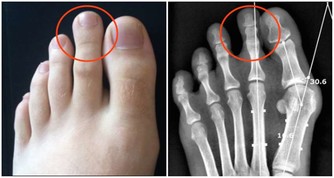

一般來說,剛出生的嬰兒大多有輕度的遠視,約75~150度左右,屬於正常的生理現象,隨年齡增長,遠視度數會逐漸降低,通常約3歲時會降到剩75度、 5歲會降到50度,至6歲時會降到沒有度數的正視1.0。若小朋友的遠視度數超過150度,就屬於高度遠視,一般需要到眼科做矯正,例如佩戴遠視眼鏡,或到醫院做遮眼訓練,也就是兩眼輪流遮住,強迫沒遮住那隻眼使用,促進眼部發育。

弱視的治療黃金期為3到6歲,因此每位小朋友在滿3歲到4歲以前,建議都要到眼科做一次完整的檢查,無論是弱視、遠視或近視,才能早期發現早期治療。若經醫師診斷確認高度遠視造成弱視,則應該及早佩戴正確度數治療。

要注意,高度遠視孩童若錯過適時診斷和治療,長期下來會因為睫狀肌過度用力,容易造成眼睛內聚, 形成所謂的鬥雞眼;還會因一直接收模糊影像,可能使視覺中樞發育不全,造成弱視的嚴重後果。因此爸媽一定要把握住六歲前的黃金治療期!